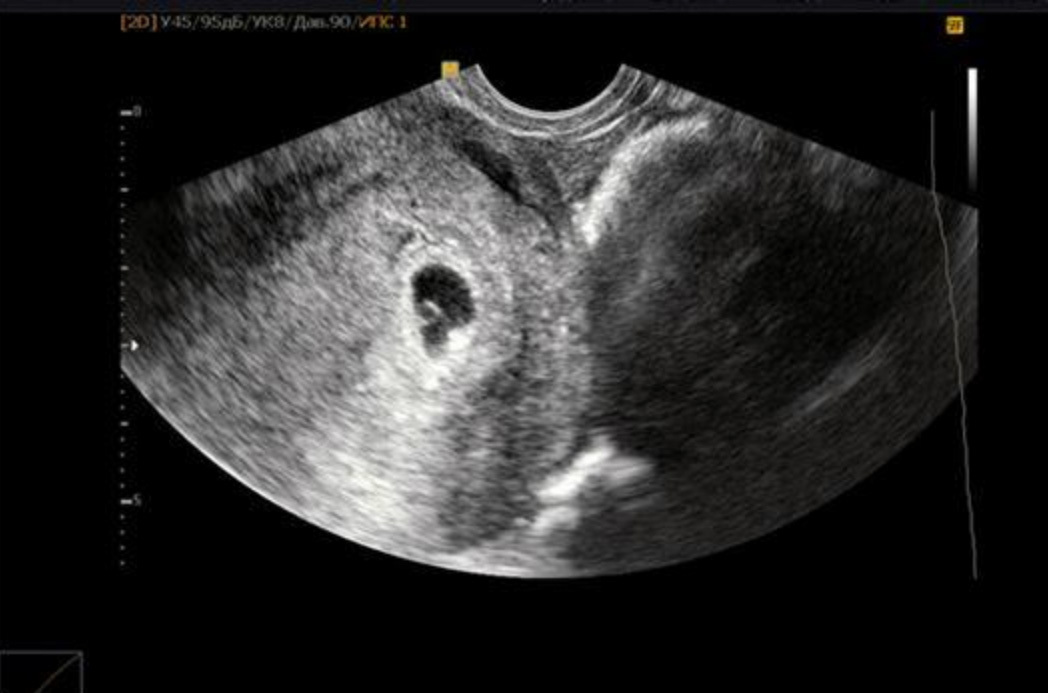

8-я неделя На этой неделе могут сделать первое УЗИ, чтобы убедиться, что беременность маточная и прогрессирует. Продолжают формироваться черты лица и внутренние органы ребенка. Будущий малыш уже начинает двигаться.

11-я неделя В это время проводят первый скрининг, который включает УЗИ и анализ крови мамы, который покажет риски генетической патологии плода и основные осложнения течения беременности. Такое обследование позволяет вовремя выявить грубые нарушения и пороки развития плода.